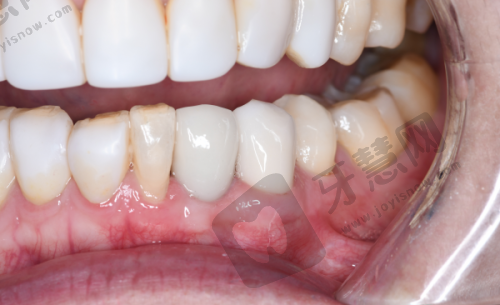

特色项目优势:北京欢乐将臣口腔门诊部的特色项目丰富多样。牙齿修复项目采用精良材料和技术,能根据患者不同牙齿情况进行个性化修复。例如种植牙修复,稳定性高、舒适度好,几乎与真牙无异,有效修复牙齿咀嚼功能。牙齿美白项目采用安心效率高美白技术,短时间内显著提升牙齿洁白度,且对牙齿损伤小。正畸项目方面,医生会根据患者牙齿畸形程度制定专属矫正方案,传统金属牙套矫正和隐形矫正都能达到理想成效,隐形矫正更因美观、舒适、可自行摘戴等优势受到特别多患者青睐,为患者带来良好的口腔诊疗体验。

北京欢乐将臣口腔门诊部在周边具有良好口碑,不少患者对其服务和诊疗成效给予肯定。顾客A实例:“我之前牙齿有缺失,一直想做修复。来到北京欢乐将臣口腔门诊部后,医生给我详细介绍了种植牙的方案。整个种植过程非常顺利,医生技术不错,术后也没有什么不适。现在牙齿用起来和真牙一样,非常感谢这里的医生和护士,服务也特别贴心。”顾客B实例:“我一直对自己的牙齿颜色不满意,就来这里做牙齿美白。医生根据我的牙齿情况制定了合适的方案,美白成效特别明显,而且过程中没有疼痛感。门诊部的环境也特别干净整洁,让人感觉特别舒适。以后看牙还来这里。”